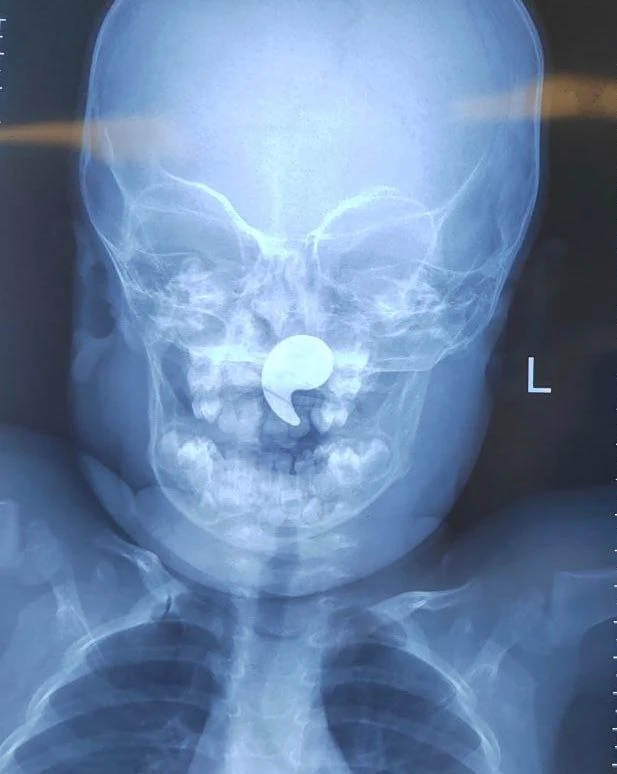

Рентген подтвердил наличие инородного тела. Девочку госпитализировали в ЛОР-отделение.

Выяснилось, что малышка играла магнитом в форме запятой. В какой-то момент она начала задыхаться, и мама попыталась извлечь предмет пальцем. После этого магнит сместился глубже — в носоглотку.